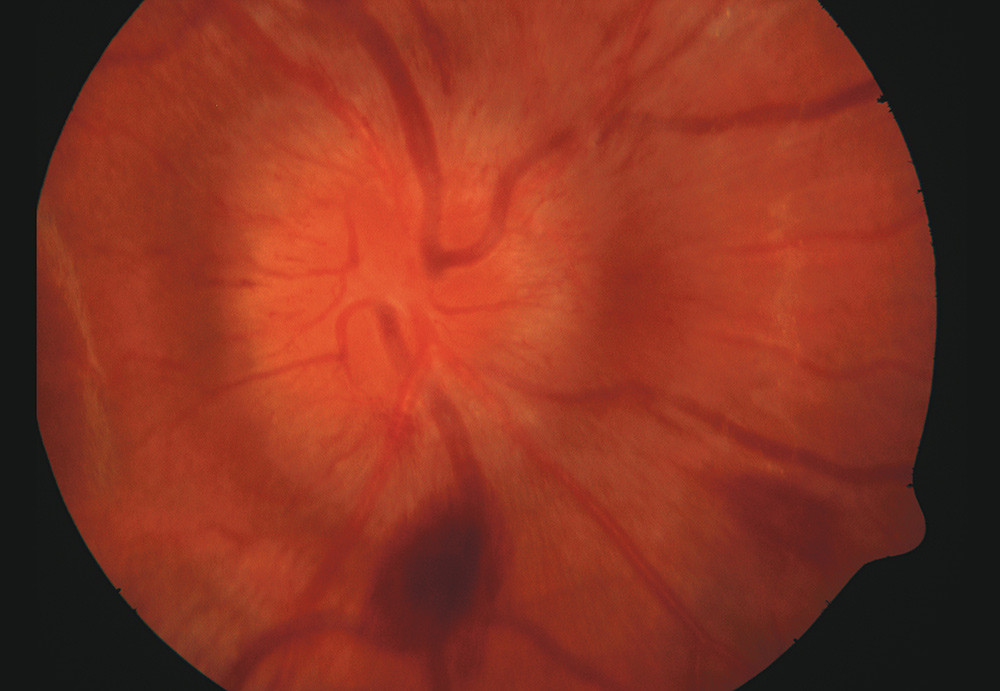

A man in his twenties was admitted to hospital with headache, dizziness, vomiting, lethargy and weight loss. Cerebral MRI showed diffuse, confluent changes in white matter, consistent with cerebral vasculitis. Conventional angiography with selective injection in both carotids and the right vertebral artery showed normal arteries with no calibre changes or occlusions. Cerebrospinal fluid tests showed an elevated number of mononuclear cells, by far the majority of which were mature lymphocytes, with 107 leukocytes per cubic millimetre (≤ 5 leukocytes per mm³) and elevated total protein 0.94 g/l (0.10 – 0.40 g/l). An eye examination showed moderate papilloedema, normal vision and no visual field defects.

Several weeks later the patient again became acutely ill, and new cerebral infarctions were detected. He now had visual disturbances and there were visual field defects in both eyes. An eye examination revealed increasing papilloedema with fresh bleeding around the papilla in both eyes. The picture shows papilloedema and bleeding in the right eye. Unfortunately we have no pictures of the peripheral retina. The patient again improved following treatment with steroids and cyclophosphamide. One month later the papilloedema and retinal bleeding had disappeared and there was only a small visual field defect.